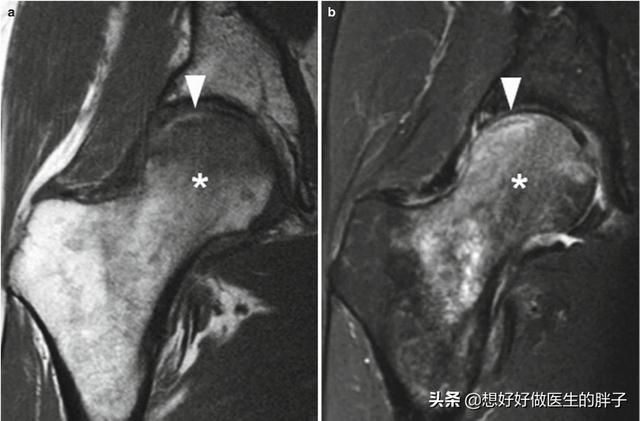

当盂唇撕裂以后或者是受伤以后会继发髋关节的滑膜炎症,这就会导致髋关节的积液。而且髋关节本身发生撞击就会诱发髋关节内滑膜的炎症,也是导致积液的原因之一。另外大家可以想象两个骨头之间相撞反复的刺激,怎么可能不会发生水肿呢?我们如果用自己的手掌敲打一个硬的桌面是不是也会发生肿胀啊?这个道理是相通的。通常情况下这种核磁表现是这样的,下图当中这些白色的箭头所示的区域就是撞击导致的水肿。

而下面这张图是髋关节撞击导致的盂唇撕裂的影像学资料,同时关节腔内有较大量的积液。